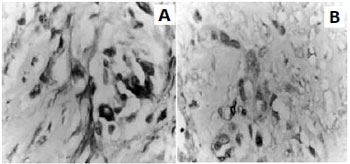

Qualitativamente, a reaçao imuno-histoquímica revelou importante diferença na sensibilidade da reaçao ao compararmos os dois métodos de fixaçao. Assim, observou-se que os cortes fixados em álcool apresentaram maior intensidade da expressao citoplasmática das células imunomarcadas, maior definiçao dos contornos vasculares e menor formaçao de

background quando comparados aos cortes do mesmo tecido fixado em formol.

2 respectivamente, ou seja, com média de positividade 80% maior no mesmo material quando fixado em álcool a 70%, com significância estatística (p< 0,01). Obteve-se, assim, significativa melhora na visualizaçao das células pesquisadas, tanto do ponto de vista qualitativo como quantitativo, como demonstram a Tabela 1 e as Figuras 1 e 2.

Figura 1 - Visualizaçao dos miofibroblastos em cortes histológicos do mesmo tecido de granulaçao, submetidos à fixaçao em álcool (A), e em formol (B) - aumento de 400X.